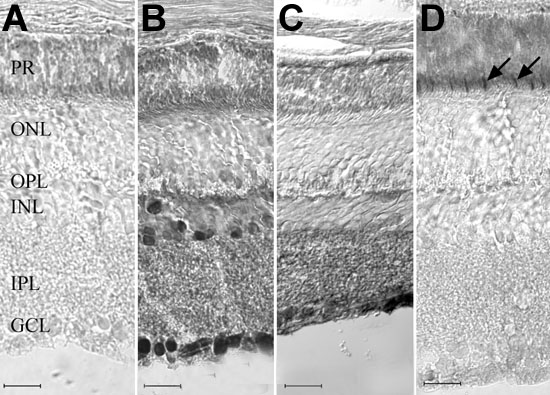

Figure 1. Immunolocalization of CNTFRα in the adult mouse retina

A: Negative control. B: Pattern of immunoenzymatic labeling with the anti-chick CNTFRα antibody. C: Pattern of immunoenzymatic labeling with the anti-rat CNTFRα antibody. D: Sequential section (to B) labeled with mouse cone arrestin antibody. E: Immunofluorescence labeling (overlaid images) with the anti-chick CNTFRα antibody (green), DAPI (blue), and peanut agglutinin (red). Intense labeling with the CNTFRα antibodies (B,E) was limited to ganglion cells, nerve fibers, and cells located predominantly at the vitreal and scleral borders of the inner nuclear layer (INL). Less intense labeling was also present at the inner plexiform layer (IPL) and outer plexiform layer (OPL). Nonspecific staining was observed at the photoreceptor layer (A-C) and was distinct from the specific cone inner segment labeling (arrows in D) obtained with the mouse cone arrestin antibody. Fluorescence immunocytochemistry confirmed the absence of photoreceptor labeling with the anti-chick CNTFRα antibody (E). Scale bars represent 20 μm (A-D) or 40 μm (E).